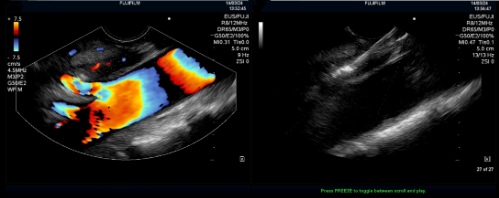

超声内镜定位腹腔神经节(左)及穿刺注射无水乙醇(右)治疗顽固性腹痛

手术当天,在超声内镜的引导下,黄永辉准确定位腹主动脉与腹腔干夹角的腹腔神经丛,通过穿刺注入2%利多卡因5ml和15ml无水乙醇,使神经节毁损而达到止痛作用,仅仅用时十分钟手术便顺利结束。